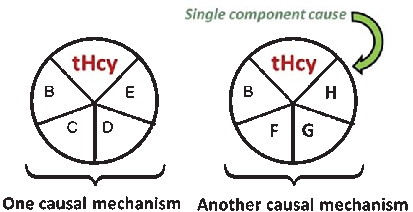

A causal model illustrates how elevated plasma homocysteine may contribute to dementia through multiple pathways, interacting with other risk factors such as age, hypercholesterolemia, and genetic predisposition. No single factor is sufficient alone; rather, combinations of component causes drive disease.

Homocysteine and Dementia: An International Consensus Statement.